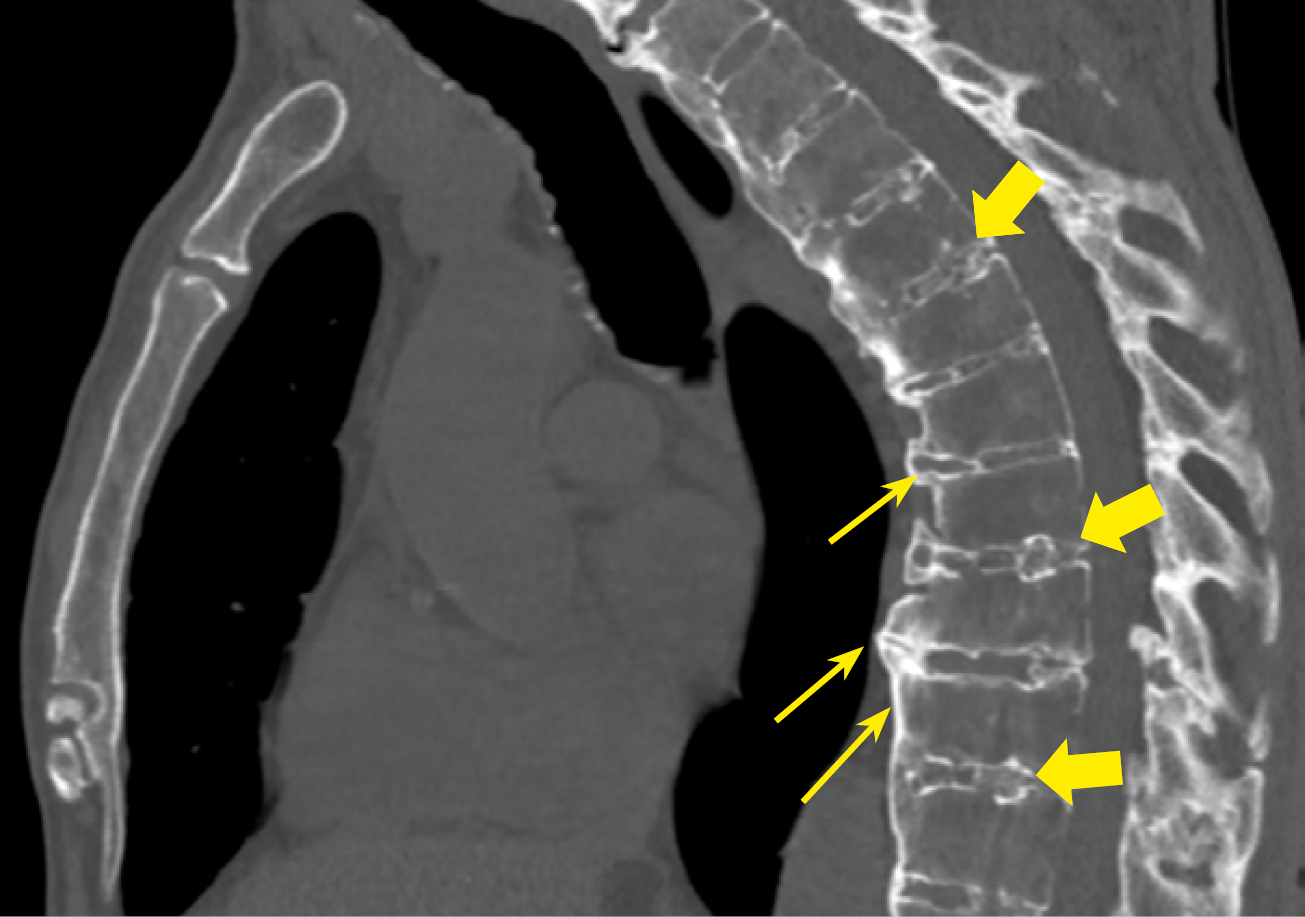

В нашем исследовании проведен анализ патологии позвоночника и суставов у пациентов с акромегалией. Спондилоартроз выявлен почти у всех пациентов — 95,9%, чуть реже визуализирован ОА реберно-позвоночных суставов 89,8% и ОА грудино-реберных суставов в 75,9% случаев (табл. 3, рис. 2–5).

Рисунок 5. МСКТ пациента А. с акромегалией 37 лет, сагиттальная проекция. Остеохондроз грудного отдела позвоночника. Остеофиты по контурам тел позвонков, формирующие «костные мостики» (стрелки), клиновидная деформация тел позвонков, снижение высоты межпозвонковых дисков, участки обызвествления в межпозвонковых дисках (толстые стрелки).

Figure 5. MSCT of patient A. with acromegaly, 37 years old, sagittal view. Osteochondrosis of the thoracic spine. Osteophytes along the contours of the vertebral bodies, forming "bony bridges" (arrows), wedge-shaped deformity of vertebral bodies, decreased height of intervertebral discs, areas of calcification in intervertebral discs (thick arrows).